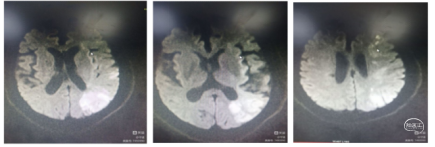

患者男,59岁,右侧肢体活动不灵1小时25分钟。神经系统:神志清楚,反应迟钝,言语基本流利,双侧额纹、鼻唇沟对称,伸舌左偏,四肢肌张力正常,右上肢肌力3级,右下肢肌力2级,右侧巴氏征(+)。NIHSS评分9分。 ASPECTS-CT评分:前循环9分。MRI显示左侧大脑前动脉区域埂塞可能,MRA大脑前动脉A2以远未显影。

造影右侧大脑前动脉缺如(未发育),左侧大脑前A2段闭塞。

1、微导丝越过闭塞处到达A3段。下图1

2、5F 125中间导管辅助高到位下图2。

3、手推造影明确血栓位置下图3。

4、微导管到达A4段下图4。

5、3*20取栓支架到位回撤微导管,多点显影标记,清晰可见支架打开良好下图5。

造影显示血管再通。

患者预后

术后14天,神经系统:神志清楚,高级智能检查正常,言语基本流利,

双侧额纹、鼻唇沟对称,伸舌左偏,四肢肌张力正常,右上肢肌力4级,

右下肢肌力3级,右侧巴氏征(+)。NIHSS评分:3分。